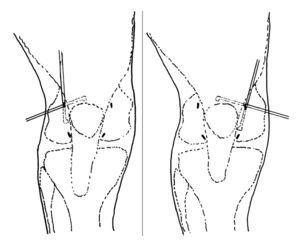

En todos los pacientes se practicó una artroscopia diagnóstica en el transcurso de la cual se realizó una denervación rotuliana artroscópica10. Los portales utilizados han sido los habituales (anteroexterno y anteromedial): a través de la vía anteroexterna es posible visualizar la práctica totalidad de las carillas articulares de la rótula. Estos portales se pueden suplementar con otros suprarrotulianos (externo e interno). El instrumental es introducido a través de las vías anterointerna o suprarrotulianas. Gracias a la combinación de los abordajes artroscópicos descritos se puede acceder a la totalidad del perímetro rotuliano para realizar una lesión térmica, con un electrocoagulador artroscópico, en el tejido blando perirrotuliano más próximo a la rótula (fig. 1). En todos los casos se ha dejado intacta (sin lesión térmica) la región que corresponde al tendón rotuliano, ya que por una parte es más difícil su visualización artroscópica por la presencia de la grasa de Hoffa, en ocasiones hipertrofiada, y por otra se ha considerado que puede comportar un alto riesgo de lesión del tendón rotuliano y de los vasos que nutren la rótula a través de él.

Figura 1.Combinando los diferentes portales suprarrotulianos y anteriores, el electrocoagulador puede acceder fácilmente al tejido blando perirrotuliano.